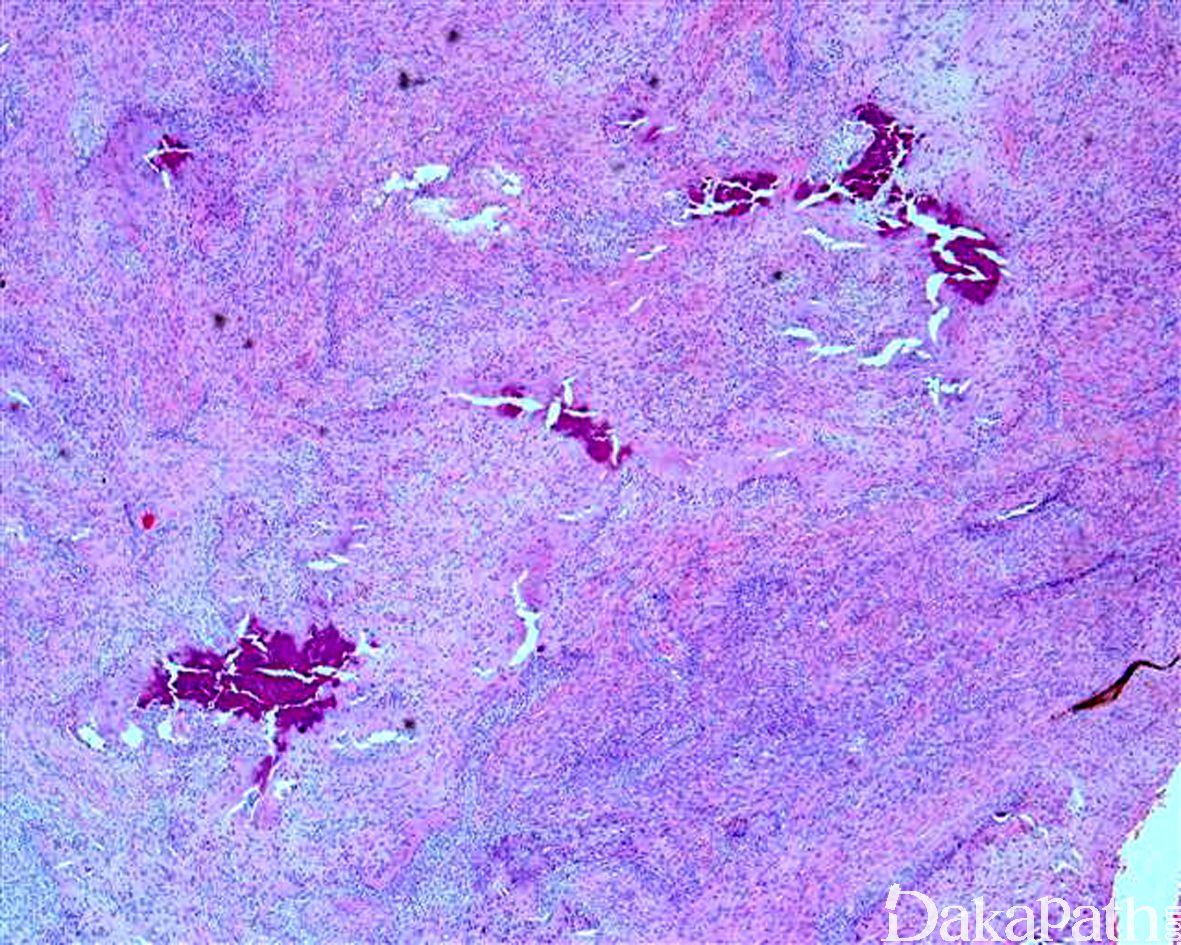

- 大体检查呈结节状或浸润性生长,位于皮下或腱鞘;

- 由胖梭形细胞栅栏状围绕软骨或点状钙化灶周围为其特征性改变;部分病例表现为梭形纤维母细胞浸 润性生长,细胞之间可见丰富的胶原纤维,两种结构可同时存在;

- 可浸润至周围的脂肪或横纹肌组织,或包绕血管和神经;